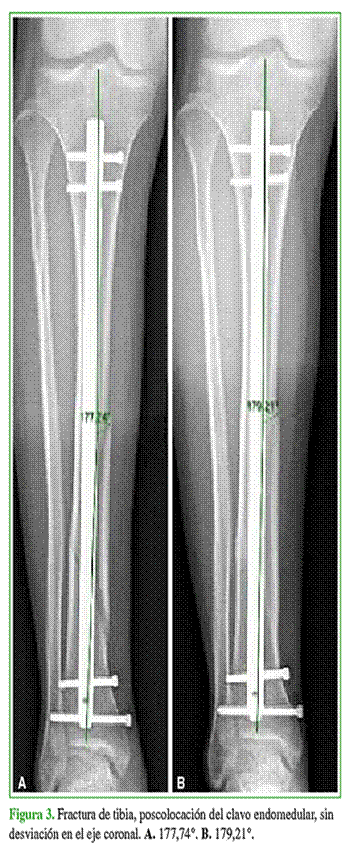

En la radiografía posquirúrgica inmediata, se observó el punto de entrada del clavo endomedular, que se clasificó en: central, medial y lateral (Figura 1), tomando como referencias radiográficas ambas espinas tibiales.

Para este procedimiento se trazó una línea vertical recta desde el punto medio de las espinas tibiales hasta el extremo distal de la tibia, por encima de la articulación tibio-astragalina (Figura 2), luego, se observó la desviación de la fractura y se la clasificó en: varo, valgo o neutra, valoración que se realizó trazando una línea recta desde las espinas tibiales hacia el centro de la diáfisis tibial y luego otra línea recta desde este último punto hasta el extremo distal de la tibia sin tener en cuenta, en este momento, los grados de desalineación.